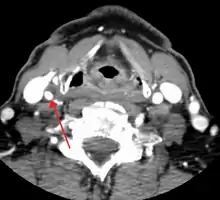

CT image of a 70 percent stenosis of the right internal carotid artery

Carotid artery stenosis is usually diagnosed by color flow duplex ultrasound scan of the carotid arteries in the neck. This involves no radiation, no needles and no contrast agents that may cause allergic reactions. This test has good sensitivity and specificity.[8]

Typically duplex ultrasound scan is the only investigation required for decision making in carotid stenosis as it is widely available and rapidly performed. However, further imaging can be required if the stenosis is not near the bifurcation of the carotid artery.

One of several different imaging modalities, such as a computed tomography angiogram (CTA)[9][10][11] or magnetic resonance angiogram (MRA) may be useful. Each imaging modality has its advantages and disadvantages - Magnetic resonance angiography and CT angiography with contrast is contraindicated in patients with chronic kidney disease, catheter angiography has a 0.5% to 1.0% risk of stroke, MI, arterial injury or retroperitoneal bleeding. The investigation chosen will depend on the clinical question and the imaging expertise, experience and equipment available.[12]